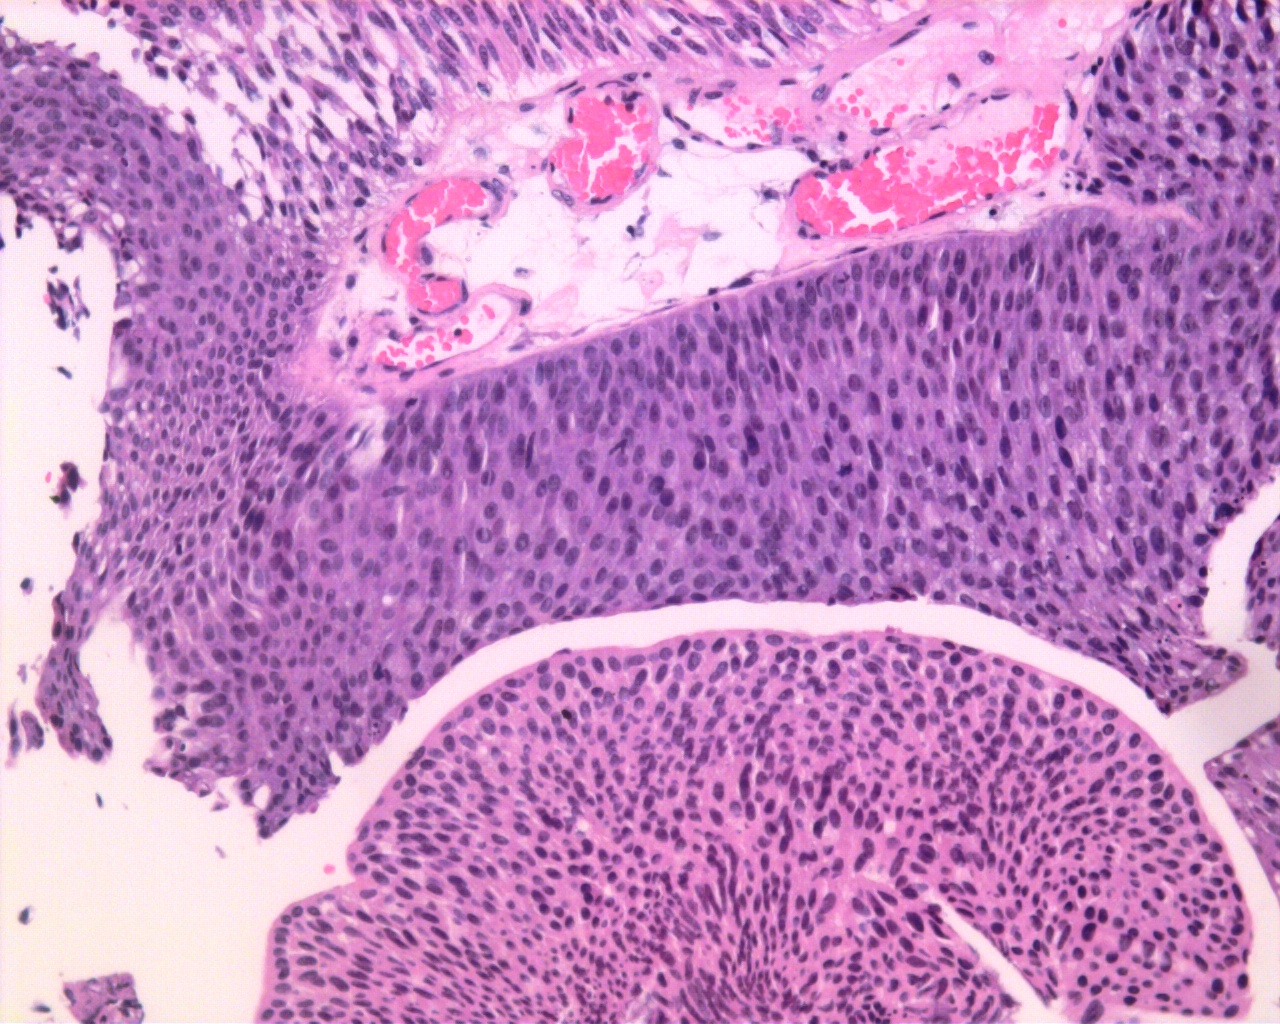

Consensus grade: Low-grade papillary urothelial carcinoma (LG-PUC)

Case description (by case creator):